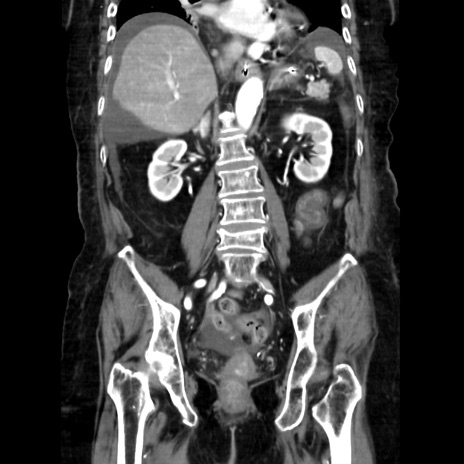

症例40(冠状断像)

【症例】90歳代女性

【主訴】腹痛・嘔吐

【現病歴】 食欲低下、嘔吐があり昨日他院受診。肺炎と診断され入院となる。入院後より腹部全体に圧痛あり。胃管留置され経過みていたが、症状持続するため、

当院転院となる。

【既往歴】胸椎圧迫骨折、胆石症

【身体所見】腹部:中央に激痛あり、圧痛あり、反跳痛不明

【データ】WBC 17100、CRP 18.82

冠状断像